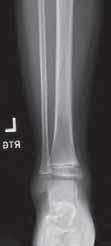

17.3.2.4. Złamania bliższej przynasady piszczeli (złamanie Cozena)

Złamania bliższej przynasady piszczeli występują rzadko (11% złamań piszczeli u dzieci), najczęściej w wieku pomiędzy 3. a 6. rokiem życia. Szczelina złamania ma zwykle przebieg poprzeczny. Często jest to złamanie typu zielonej gałązki. Może mu towarzyszyć złamanie kości strzałkowej lub jej deformacja plastyczna. Nie zdarza się często, ale ma duże znaczenie kliniczne, ponieważ może prowadzić do postępującej koślawej deformacji kończyny. Do złamania dochodzi najczęściej w mechanizmie urazu, którego siła działa od boku na kończynę wyprostowaną w stawie kolanowym.

Rozpoznanie

W badaniu klinicznym dominują ból i obrzęk okolicy bliższej przynasady piszczeli, bolesne ruchy bierne w stawie kolanowym. Może być widoczna deformacja koślawa. Ruchy czynne są zniesione. Należy dokładnie zbadać ukrwienie i unerwienie kończyny z powodu ryzyka wystąpienia zespołu ciasnoty przedziałów powięziowych. Złamanie można sklasyfikować jako poprzeczne, skośne, zielonej gałązki, deformację plastyczną, złamanie typu torus Badanie RTG wykonujemy w pozycji AP i bocznej. Bardzo pomocne może być wykonanie badania TK.

Leczenie

Leczenie polega na zamkniętej repozycji oraz unieruchomieniu w opatrunku gipsowym udowym z kolanem ustawionym w całkowitym wyproście.